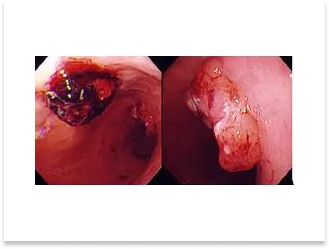

術前内視鏡写真

切除標本